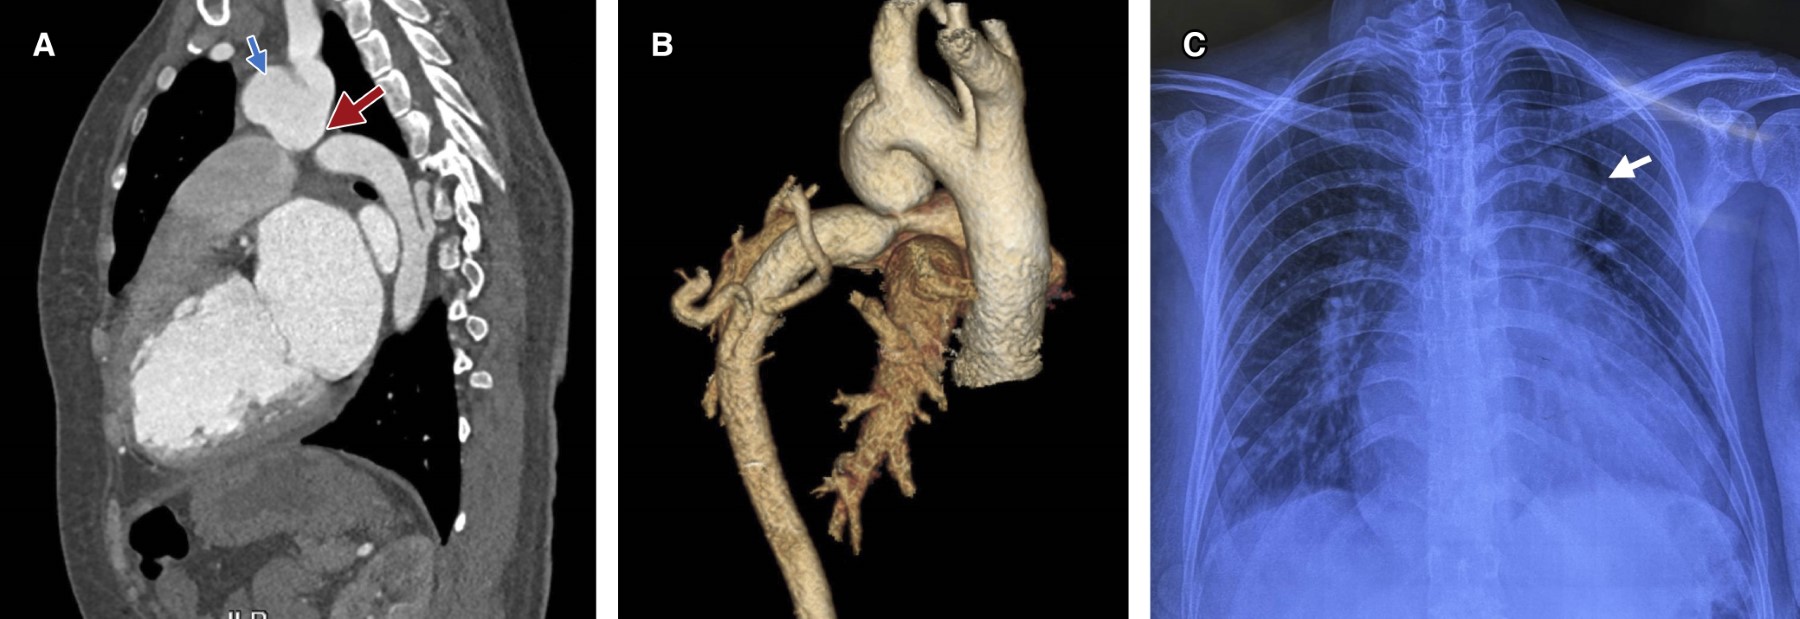

For surgical resolution the sternotomy approach was performed. A 7 mm dacron graft anastomosis is performed at the right subclavian level. Arterial cannula of 19 mm is placed. Sternotomy is performed, finding multiple collateral vessels, subsequent opening of the pericardium, supra-aortic trunks are surrounded. Bicaval venous cannulation is performed. Heparinization and initiation of cardiopulmonary bypass. Temperature decreases to 28 °C, emptying (continuous retrograde perfusion through the brachiocephalic trunk). Aortic clamping and initiation of cardioplegia. Supra-aortic trunks and aortic isthmus are dissected up to their most distal portion. Aneurysm with fistula to the pulmonary artery trunk is identified. Aneurysm dissection of distal end of interruption of the aortic arch is performed, as well as pulmonary artery trunk identifying conduit. The aneurysm is resected, the pulmonary trunk is opened, the duct is sectioned and the descending aorta is identified. A 20 mm dacron graft is placed after placing the bigoteral in the distal end of the aortic mouth performing anastomosis with prolene 3-0 surgete, proximal anastomosis same technique (Figure 3). After clamping, bleeding occurred at the distal site of the anastomosis, so a 26 × 10 mm zenith endoprosthesis was positioned under fluoroscopy. Hemostasis was corroborated, epicardial cables, drains and sternal closure were placed. The findings were aneurysm in proximal end of 5 × 8 cm, interruption of the aortic arch type A and type I truncus arteriosus without ventricular septal defect. The pump time was 3 hours and 28 minutes and the aortic clamping time was 2 hours and 2 minutes. After surgery, the patient was admitted to the intensive care unit (Figure 4). He died fourteen days after surgery due to septic shock.

Figure 3

Figure 4